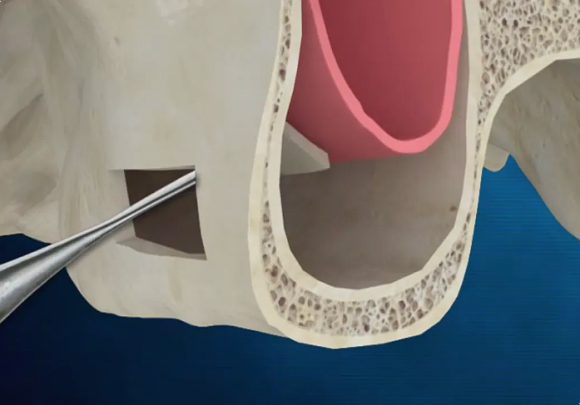

또한 왼쪽 위 어금니는 발치 후 잇몸뼈가 부족뿐만 아니라, 상악동이라는 공기주머니와 가까운 위치에 있어 측면 접근법 상악동 거상술이라는 난도 높은 수술과 임플란트 골이식이 필요했는데요.

이 과정은 상악동의 얇은 막을 조심스럽게 들어 올려 인공 뼈를 이식하는 매우 정교한 기술로 수술 경험과 전문성이 필요한 시술이지만,

상악동거상을 위해 측면 골을 열고 조심스럽게 올리는 모습